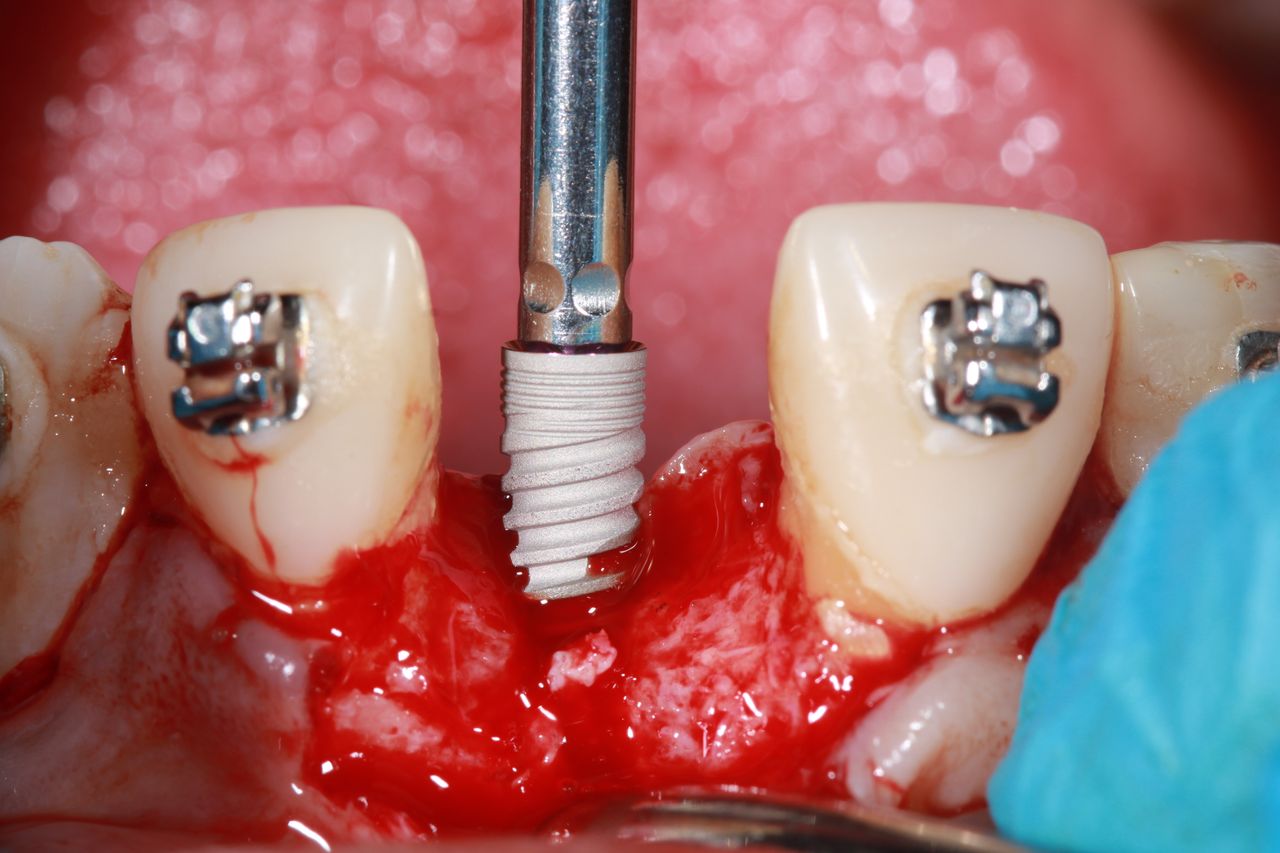

Especialista en Implantología Oral quirúrgica y protesica, cédula de especialidad: 12411844

La especialidad en Implantología Oral se enfoca en sustituir órganos dentarios perdidos por implantes dentales mediante una fase quirúrgica y una fase protesica y de esta manera devolver la función, estetica y confort dental del paciente.